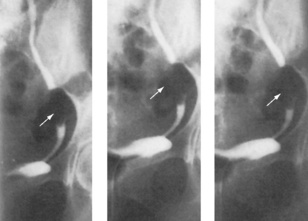

Micturating cystourethrograms are used to demonstrate vesicoureteric reflux from the bladder to the ureters during emptying of the bladder (Fig. 8.26). Reflux can be classified into three grades.

Grade 1: contrast medium enters the ureter only

Grade 2: contrast medium fills the pelvicalyceal system

Grade 3: dilatation of the calyces and ureter.

image

Fig. 8.26 A micturating cystourethrogram showing bilateral ureteric reflux. This patient has early calyceal clubbing (A) and ureteric dilatation (B). This is grade 3 reflux.

(Courtesy of Mr RS Cole.)

This technique was used to investigate patients with recurrent urinary tract infections but has largely been replaced by other techniques because of concerns over ionizing radiation (especially in children).